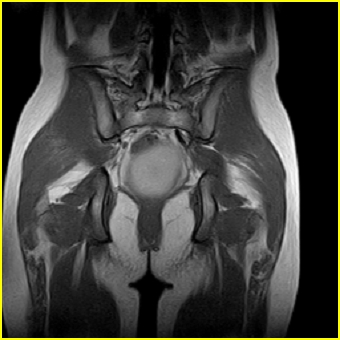

女、15岁、下腹疼痛2天,排尿困难1天。查体:处女膜闭锁,距处女膜约4至5cm处扪及一约5cm直径的圆形包块,张力较高,触痛明显、欠活动。b超提示子宫增大伴宫内增强回声团。

影像意见:子宫直肠陷凹积血。

更正影像意见:阴道积血。

处女膜闭锁,阴道积血

处女膜闭锁,阴道积血,子宫积血.

阴道积血,子宫积血.

子宫及阴道积血。

处女膜闭锁,伴子宫及阴道积血.